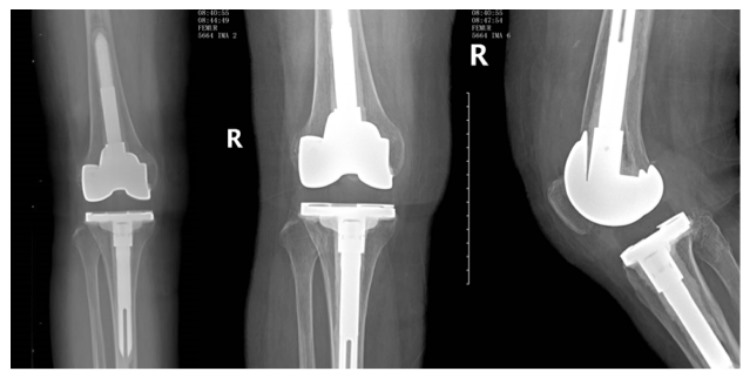

患者初次关节置换术后右膝关节正侧位X片/图源 重医附二院

经问询病史、仔细查体,以及结合临床与影像学检查,程兴旺对江婆婆的病情有了初步了解。患者右膝关节正位X片显示人工关节假体较大,部分悬挂出平台。凭借丰富的临床经验,程兴旺根据疼痛区域等“线索”,初步判断“髂胫束撞击”可能是患者膝关节疼痛的主要原因。入院后,他在患者的右膝外侧髂胫束附着点周围使用了“倍他米松+利多卡因”进行封闭治疗,疼痛症状得到短时缓解,进一步明确了患者疼痛部位。经关节中心的专家们多次讨论、反复权衡,并与患者家属沟通,取得一致意见后,拟为其行“右侧人工膝关节翻修手术”。

一系列复杂的手术操作一气呵成,程兴旺带领团队顺利完成该例复杂人工膝关节“翻修”手术,准确迅速为江婆婆安装了完全契合的人工膝关节,术后X片显示,假体稳定、位置良好。

患者人工膝关节“翻修”术后右膝关节X片/图源 重医附二院

术后第1天,困扰江婆婆近2年的疼痛明显缓解,膝关节屈伸过程中无明显疼痛感;术后第2天,即可主动进行膝关节屈、伸功能锻炼;术后第3天,可在助行器辅助下下地练习行走。一周后,江婆婆“欢天喜地”地出院了,“终于不再受关节疼痛的折磨,真的太感谢程医生了!”